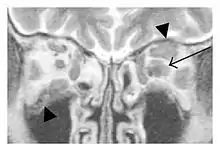

Infraorbital nerve enlargement (IONE) is considered to be a particularly suspicious sign of IgG4-ROD, but seems to occur only when inflammation is in direct contact with the infraorbital canal.[10] IONE is defined as the infraorbital nerve diameter being greater than the optic nerve diameter in the coronal plane.

![]() Enlargements in the left inferior rectus muscle and infraorbital nerve (arrow) in a 65-year-old man with a serum IgG4 of 404 mg/dL.[1] (T2-weighted MRI) |

![]() Bilateral supraorbital nerve enlargements (arrows) and right infraorbital nerve (arrow head) enlargement in a 47-year-old woman with a serum IgG4 of 1000 mg/dL.[1] (T1-weighted MRI) |